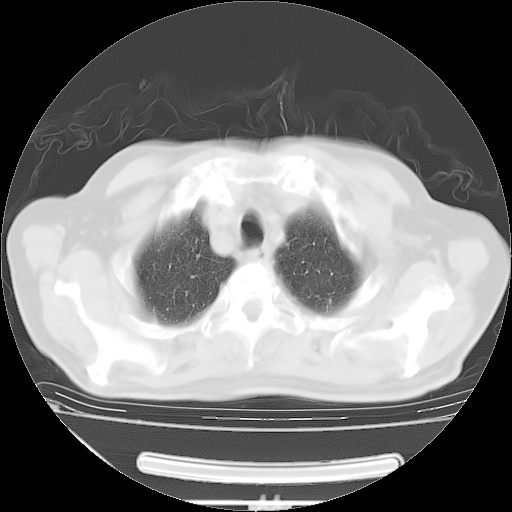

今天复查肺部CT,发现双肺广泛磨玻璃样改变。所以我把3月19日和5月9日相隔50天的肺部CT上传。请大家会诊。

5月9日肺部CT(在4月27日齐鲁医院肺部CT描述部分肺组织磨玻璃样改变,12天后肺组织广泛磨玻璃样改变)

2009年5月9日肺部CT

大致读了系列胸部CT:纵隔窗无明显异常,肺窗:从4、27至今:主要是双肺中下野外带可见毛玻璃样改变,目前处于急性肺泡炎阶段,至于原因考虑1、结替组织或胶原血管性疾病所致?2、恶性疾病如恶组在肺部所致的表现或细支气管肺泡癌?3、药物或其它原因如肺蛋白沉着症所致肺泡炎目前不太可能?总之,明天就去请我院的呼吸科、感染科、血液科和临免专家会诊哈。